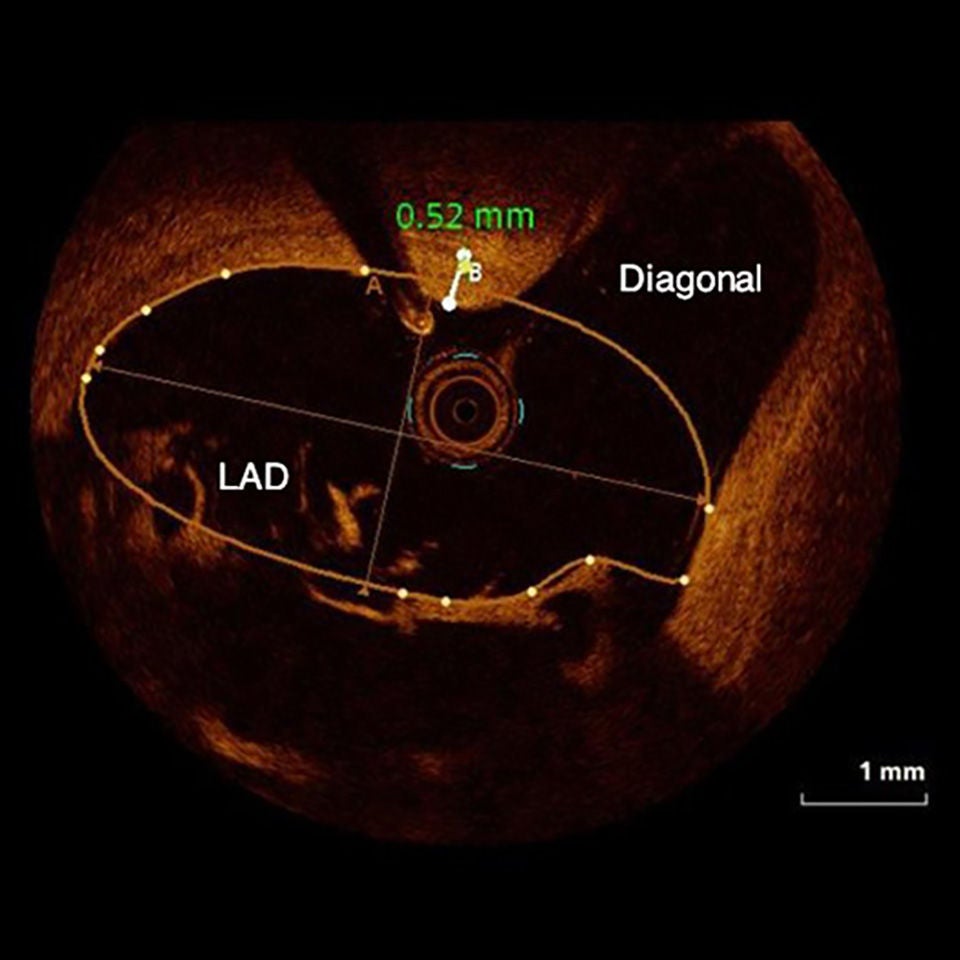

OPTICROSS HD vs. Abbott

The OPTICROSS HD Imaging Catheter has comparable resolution, low contrast usage, and better depth than Abbott's optical coherence tomography (OCT).

OPTICROSS HD Imaging Catheter 60 MHz

High-definition IVUS image of inside a coronary lesion using the OPTICROSS HD catheter

OCT

Image of the inside a coronary lesion using OCT.

OPTICROSS HD versus OCT images courtesy of Massoud Leesar, MD; Professor of Medicine; Section Head, Interventional Cardiology, Baker-Dean Endowed Professor in Interventional Cardiology, University of Alabama-Birmingham